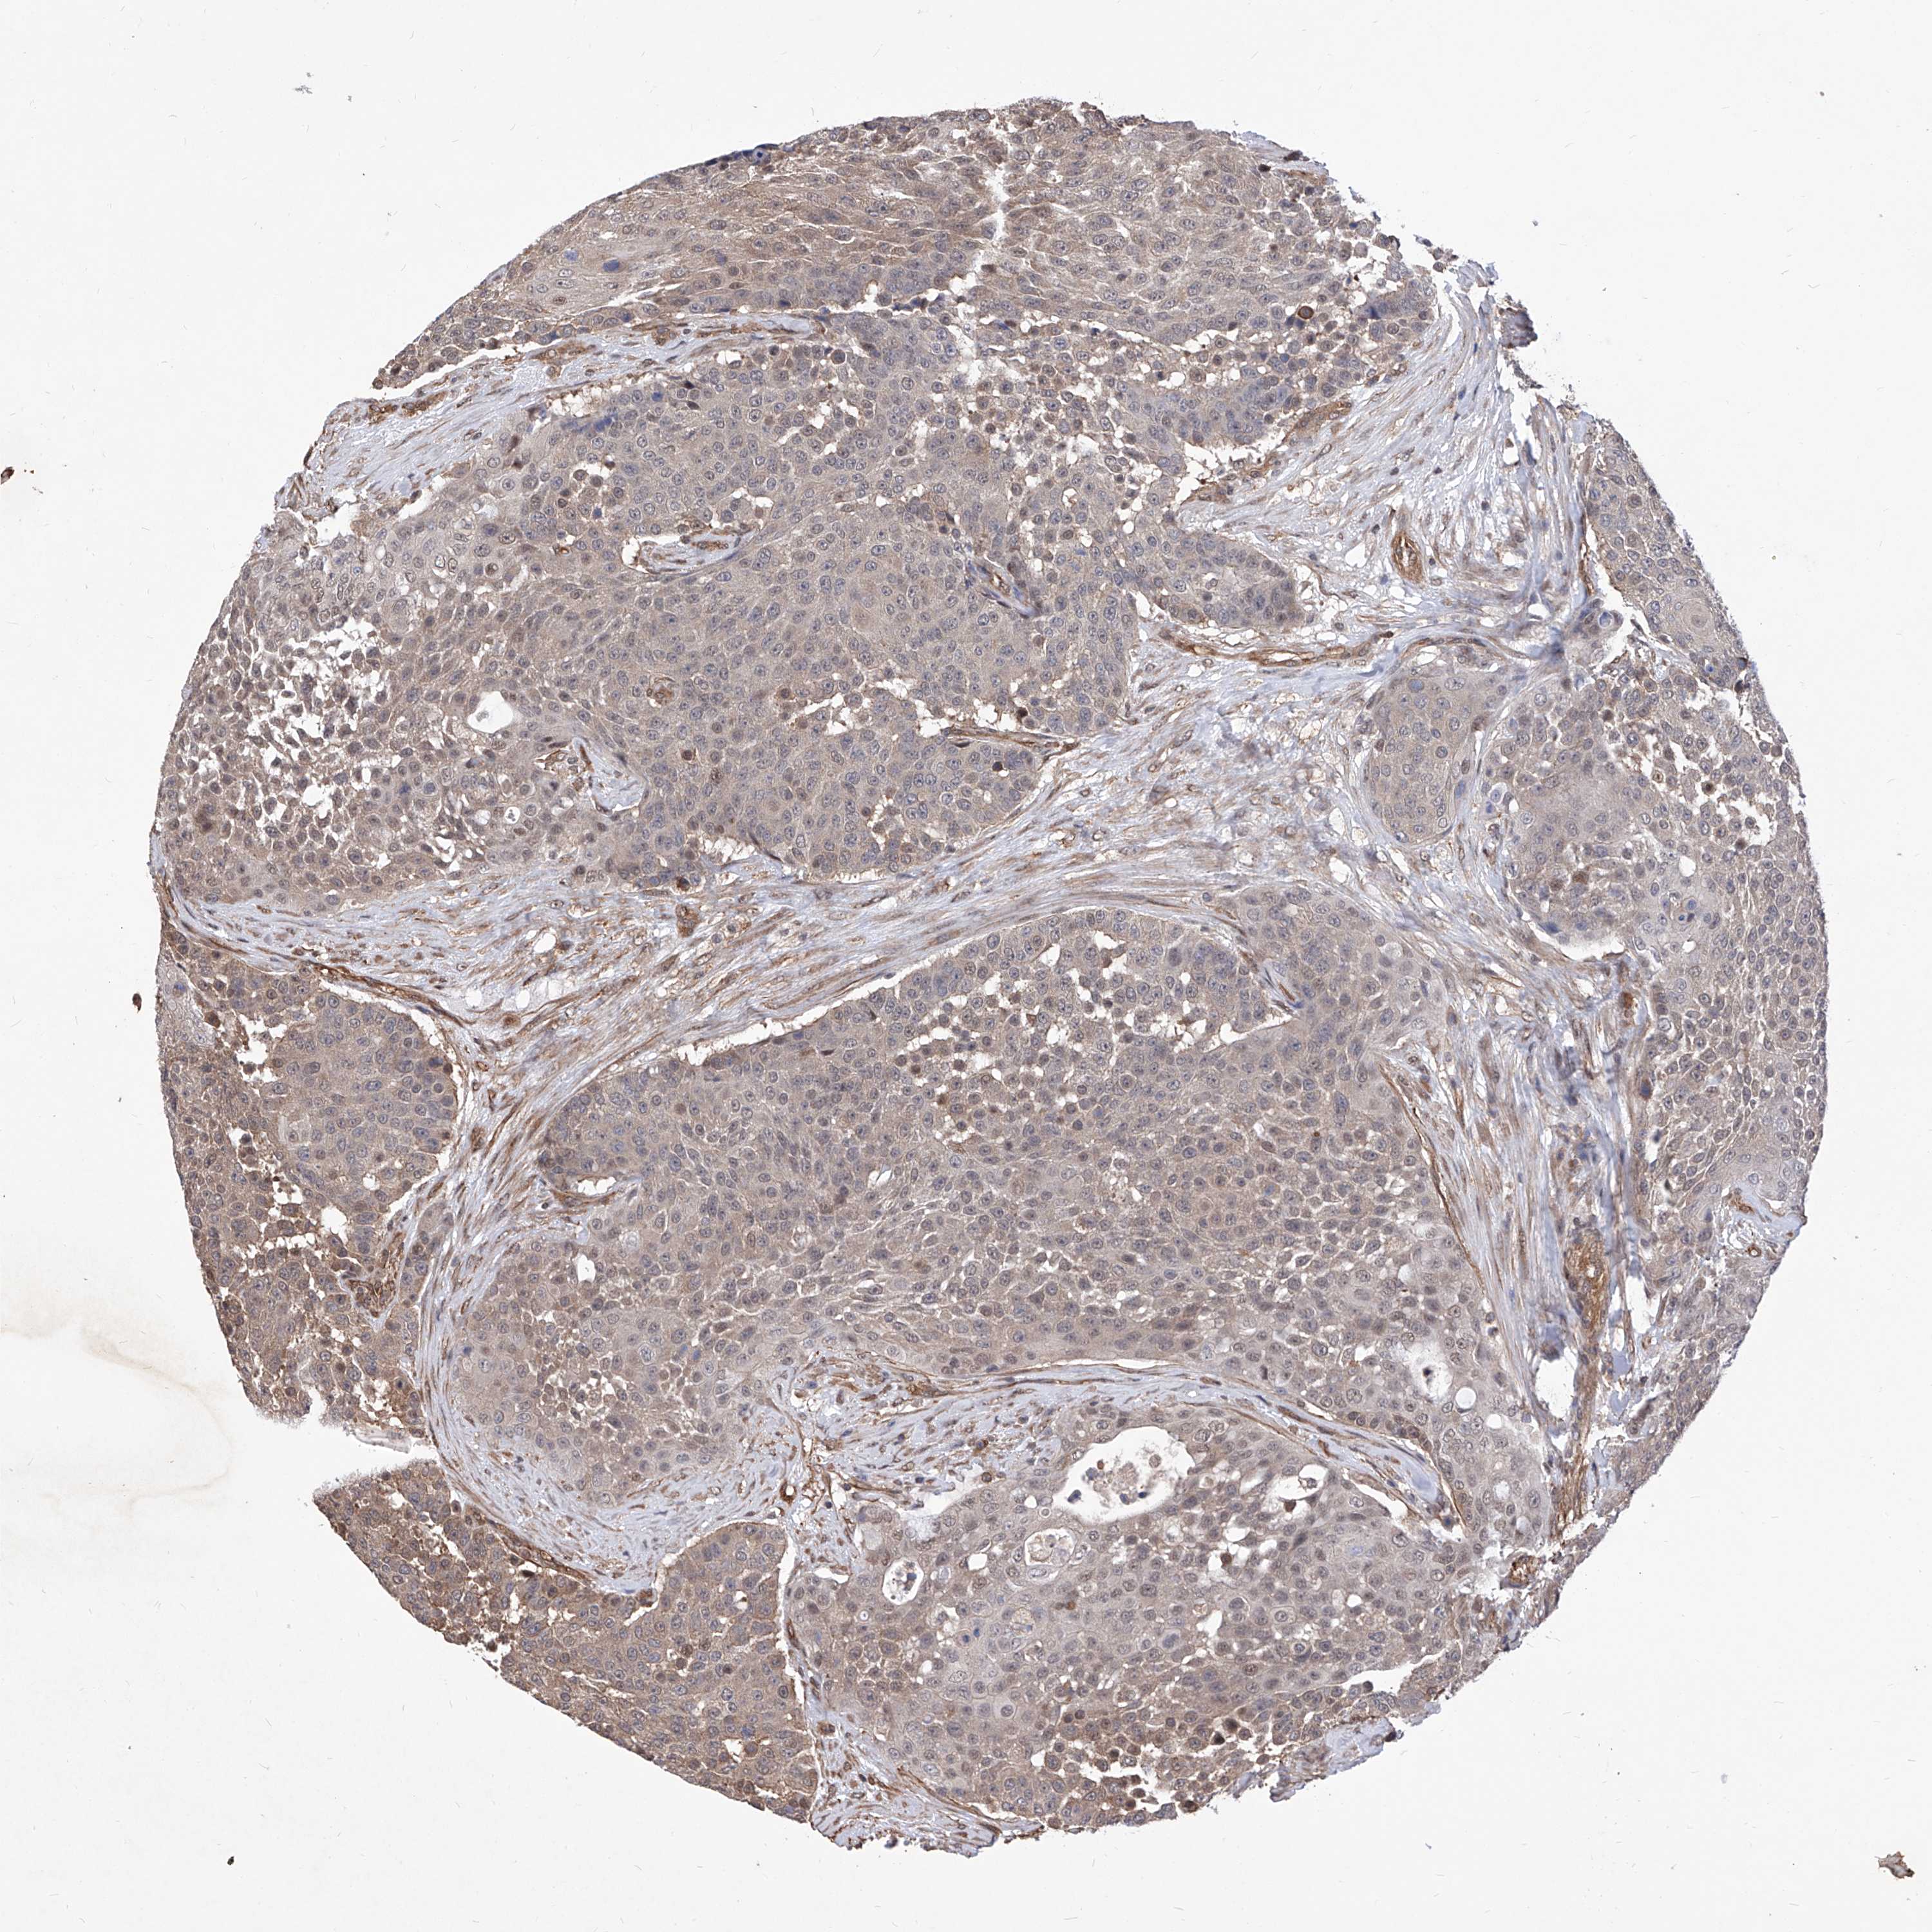

UROTHELIAL CANCER - Protein expressioni

A mouse-over function shows sample information and annotation data. Click on an image to view it in a full screen mode. Samples can be filtered based on level of antibody staining by selecting one or several of the following categories: high, medium, low and not detected. The assay and annotation is described here.

Note that samples used for immunohistochemistry by the Human Protein Atlas do not correspond to samples in the TCGA dataset.

Antibody stainingi

Antibody staining in the annotated cell types in the current human tissue is reported as not detected, low, medium, or high, based on conventional immunohistochemistry profiling in selected tissues. This score is based on the combination of the staining intensity and fraction of stained cells.

Each image is clickable and will lead to virtual microscopy that enables deeper exploration of all samples and also displays staining intensity scores, fraction scores and subcellular localization as well as patient and tissue information for each sample.

Antibody HPA029534

Staining

High

Medium

Low

Not detected

Intensity

Strong

Moderate

Weak

Negative

Quantity

>75%

75%-25%

<25%

None

Location

Nuclear

Cytoplasmic/membranous

Cytoplasmic/membranous,nuclear

Urothelial carcinoma, Low grade

Urothelial carcinoma, High grade